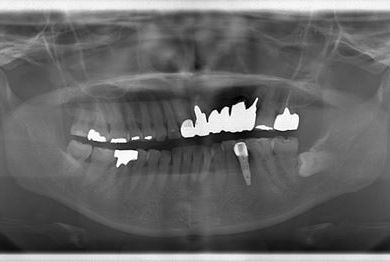

| 性別/年齢 | 女性 / 45歳 | ||||||||||||||||||||||||||||||||

| 主訴 | 以前治療した歯の歯ぐきから出膿。他の歯科でインプラントかブリッジしか方法がないが、骨の状態からインプラント治療は無理かもしれないと言われたことに不安を感じ、セカンドオピニオンを求めて来院。 | ||||||||||||||||||||||||||||||||

| 治療方針 | 保存不能の歯を抜歯し、インプラント治療にて機能的・審美的回復を行う。 | ||||||||||||||||||||||||||||||||

| 治療内容 | インプラント1本、ハイブリッドセラミッククラウン1本 | ||||||||||||||||||||||||||||||||